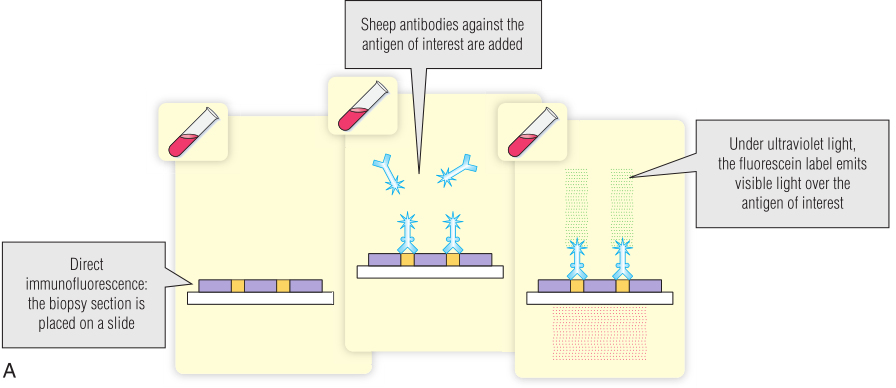

免疫荧光

免疫荧光使用的是荧光化合物(荧光素)共价连接的抗体。免疫学家广泛使用的一种荧光化合物是异硫氰酸荧光素(FITC),它与蛋白质上的游离氨基偶联。当FITC暴露在紫外线(UV)下时会发出绿色光。安装紫外线光源的荧光显微镜被用来检查暴露在荧光抗体中的样本。这项检测广泛用于检测细胞或组织切片中的抗原。它还用于筛选细胞或组织抗原的自身抗体(第28章)。要么测试抗体直接连接到荧光化合物(直接检测),要么可以识别抗体的配体连接到荧光化合物(间接检测;Fig 5.6)。通常,荧光配体是针对检测抗体(如山羊抗人免疫球蛋白)所特有的第二种抗体。BOX 5.2提供了间接免疫荧光分析的临床应用实例。

Fig 5.6 使用异硫氰酸荧光素(FITC)进行直接(A)和间接(B)免疫荧光。其他荧光染料可以与不同的颜色一起使用

为了确认潜在的献血者是否真的患有梅毒,该血清被用于特定的免疫荧光测试。如果这个结果也是阳性的,就证实这位捐赠者确实患有梅毒,她的血液不能用于输血,她还会被转介治疗梅毒。

梅毒的特异性血清学检测

梅毒螺旋体引起梅毒。这种细菌是一种柔韧的螺旋杆(Fig 5.10)。为了获得如图所示的图像,进行了荧光梅毒抗体吸收试验(FTA-ABS)。试验血清首先被非致病性梅毒螺旋体吸收,以去除交叉反应抗体。然后,将吸收的试验血清与梅毒螺旋体在显微镜载玻片上反应,根据Fig 5.6中描述的间接免疫荧光法,在荧光显微镜下用异硫氰酸荧光素(FITC)偶联的抗人免疫球蛋白G(IgG)抗体检测任何与梅毒螺旋体结合的抗体。